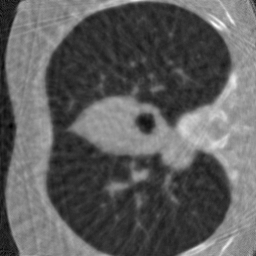

Computerized tomography

We consider parallel beam X-ray computerized tomography. It consists in probing line integrals of an object along a set of parallel lines that may be rotated and shifted. In this application the parameter represents the angles and shift at origin of the lines. The problem becomes blind if the object to image moves during the scan.

4.3.2 Computerized tomography

In this modality, we assume that the distribution of projection angles follows a uniform distribution centered on a vector of regularly spaced angles (see the red lines in first row of Fig. 1) and shift at origin . Hence, we have with and the random shifts are . These perturbations may reflect movements of the patient inside the scanner during the scan.

For CT reconstruction, we considered measurements coming from randomly perturbed versions of the equiangular pattern . The network is an unrolled ADMM ran for iterations. The perturbations belong to the family used for the family training. The perturbation is twice larger than what was observed during the training phase and does not belong to .

6.3.2 Computerized tomography

In this application, a model mismatch might occur due to the motion of a patient in the scanner. Correcting this mismatch is essential. Not accounting for it, can result in severe artifacts including some details loss and blur as can be seen in Fig. 6.

To identify the forward model, we ran the Adam optimizer on the parameters for iterations. In this application, represents the angle of the parallel shots and their shift at origin. All the reconstruction methods are able to significantly reduce the model mismatch, passing from maximal angles shifts of 7 degrees to less that 1 degree. Similarly, the shifts at origin are reduced from more than a pixel to about pixel. The reconstruction performance is significantly improved after estimating the forward model with PSNR increases of dB and more. The neural network trained on a family provides the best reconstruction results on this example.